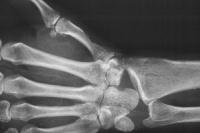

By this point, the patient has undergone proximal row carpectomy for control of infection involving the scaphoid and lunate. The capitate is visible in the depths of the wound:

Further debridement required decortication of the thumb metacarpal (see below). This defect was covered by the abductor pollicis brevis muscle, mobilized distally and rotated to the dorsum of the thumb metacarpal: